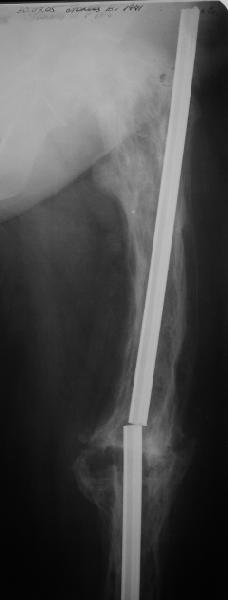

Еще один пример. Пациентка с юга России, прислала рентгенограммы через год. На сегодня прошло 2 г. 8 мес. после операции. Несмотря на не очень убедительный процесс сращения, пациентка ходит. Учитывая остеопороз при Педжете, решили, что динамизировать вообще не нужно.

При переломах на фоне болезни Педжета металлоконструкция часто служит эндопротезом, несущим нагрузку. Динамизация индивидуальна,- по рентген-динамике. Основной упор- на медикаментозную терапию- см. канд. дисс. Колондаева А.Ф.

Стержень можно было бы поставить подлиннее.